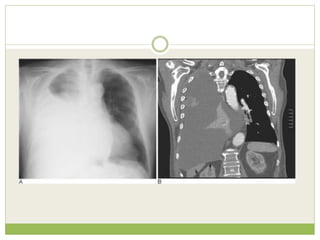

• #43ย Massive pleural effusion with mediastinal shift to the left. (A) Chest radiograph and (B) CT coronal reconstruction. A massive effusion displaces the mediastinum to the left. CT shows the important pleural effusion together with the enhanced atelectatic left lung. Note also the depression of the right hemidiaphragm (arrows).